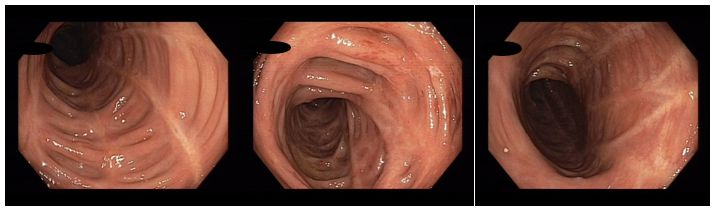

Koloskopie 2017/2: Aktivní zánětlivé změny (serpiginózní ulcerace) v oblasti rektosigmatu, mírné zánětlivé změny v blízkosti hepatálního ohbí, segmentálně pozánětlivé změny zejména v levém tračníku (jizvy, retrakce). Normální terminální ileum

Histologie: Mikroskopický nález je kompatibilní s klinickou diagnózou idiopatického střevního zánětu, resp. Crohnovy choroby, přičemž je patrna aktivita onemocnění. Dysplastické změny neprokázány